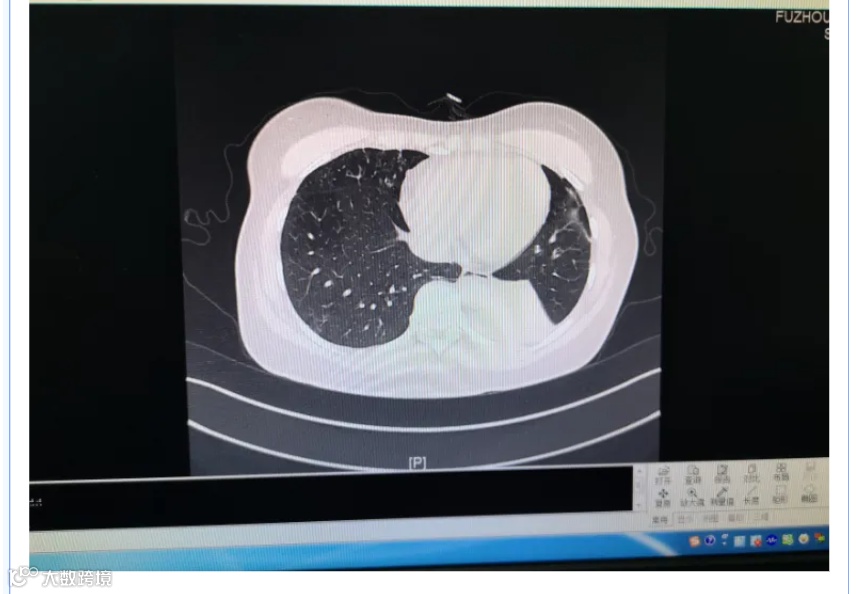

霉菌会引起肺炎!

曲霉菌菌丝入侵肺部的感染,是肺曲霉菌病中最常见、也最严重的情况,尤其是如果还存在慢性肺病,情况可能会更糟糕 。发病时会表现出发热、干咳、咯血、胸痛、呼吸困难等症状。

适宜的繁殖环境中,它们可以分生出数以万计的孢子,漂浮在空气中,随气流扩散,有的附着在墙壁、地毯、衣物、食物,木材等,而少部分的孢子则会通过呼吸道进入人体。

作为一种外来入侵物种,绝大多数的孢子会被人体免疫系统识别并清除,而对于免疫功能受损的人群来说,孢子进入呼吸道以后,会突破上皮细胞进一步生长,侵袭肺部,然后你的肺就开始“霉变”了!